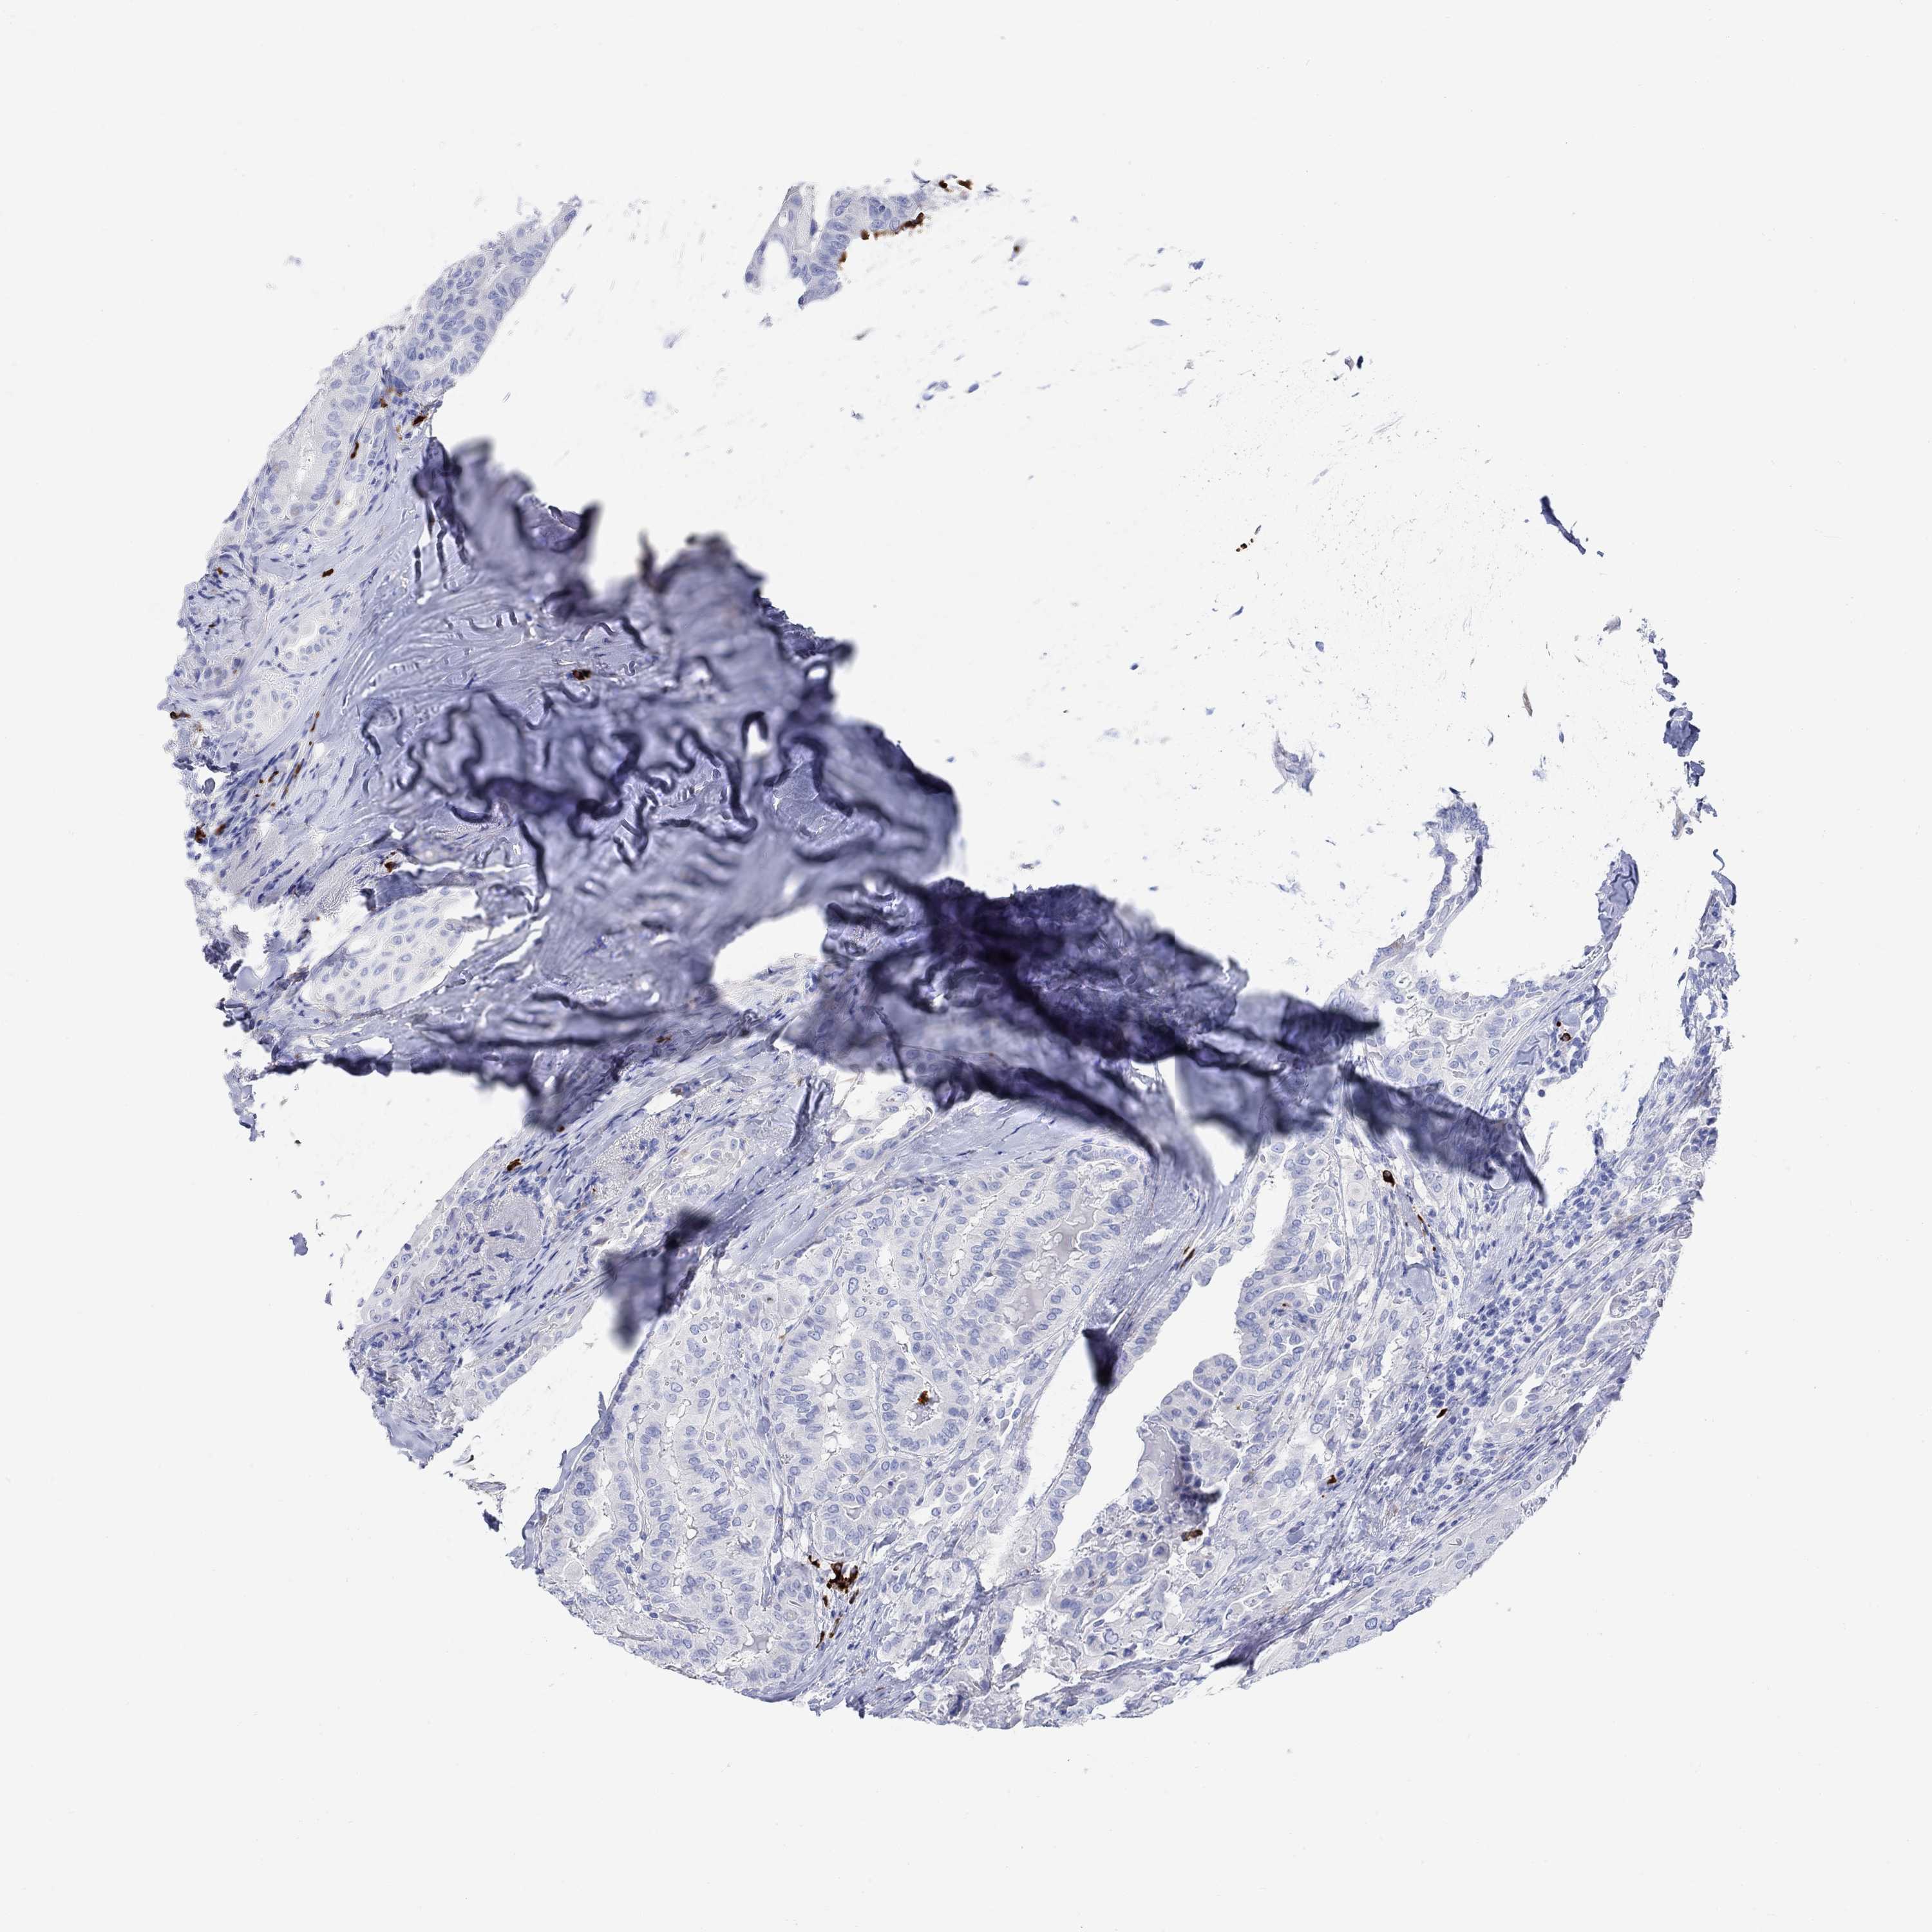

THYROID CANCER - Protein expressioni

A mouse-over function shows sample information and annotation data. Click on an image to view it in a full screen mode. Samples can be filtered based on level of antibody staining by selecting one or several of the following categories: high, medium, low and not detected. The assay and annotation is described here.

Note that samples used for immunohistochemistry by the Human Protein Atlas do not correspond to samples in the TCGA dataset.

Antibody stainingi

Antibody staining in the annotated cell types in the current human tissue is reported as not detected, low, medium, or high, based on conventional immunohistochemistry profiling in selected tissues. This score is based on the combination of the staining intensity and fraction of stained cells.

Each image is clickable and will lead to virtual microscopy that enables deeper exploration of all samples and also displays staining intensity scores, fraction scores and subcellular localization as well as patient and tissue information for each sample.

Antibody HPA074751

Staining

High

Medium

Low

Not detected

Intensity

Strong

Moderate

Weak

Negative

Quantity

>75%

75%-25%

<25%

None

Location

Nuclear

Cytoplasmic/membranous

Cytoplasmic/membranous,nuclear

Papillary adenocarcinoma, NOS

Follicular adenoma carcinoma, NOS